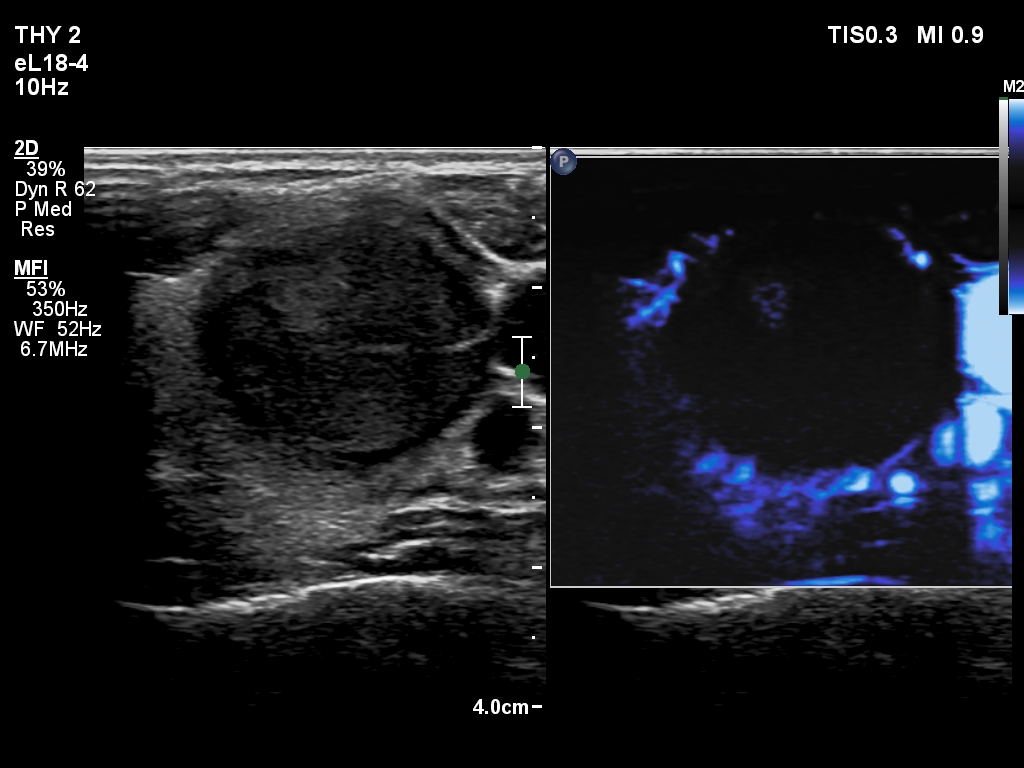

First session of sclerotherapy (ultrasonographic picture 4)

Left lobe, transverse scan, microflow imaging.